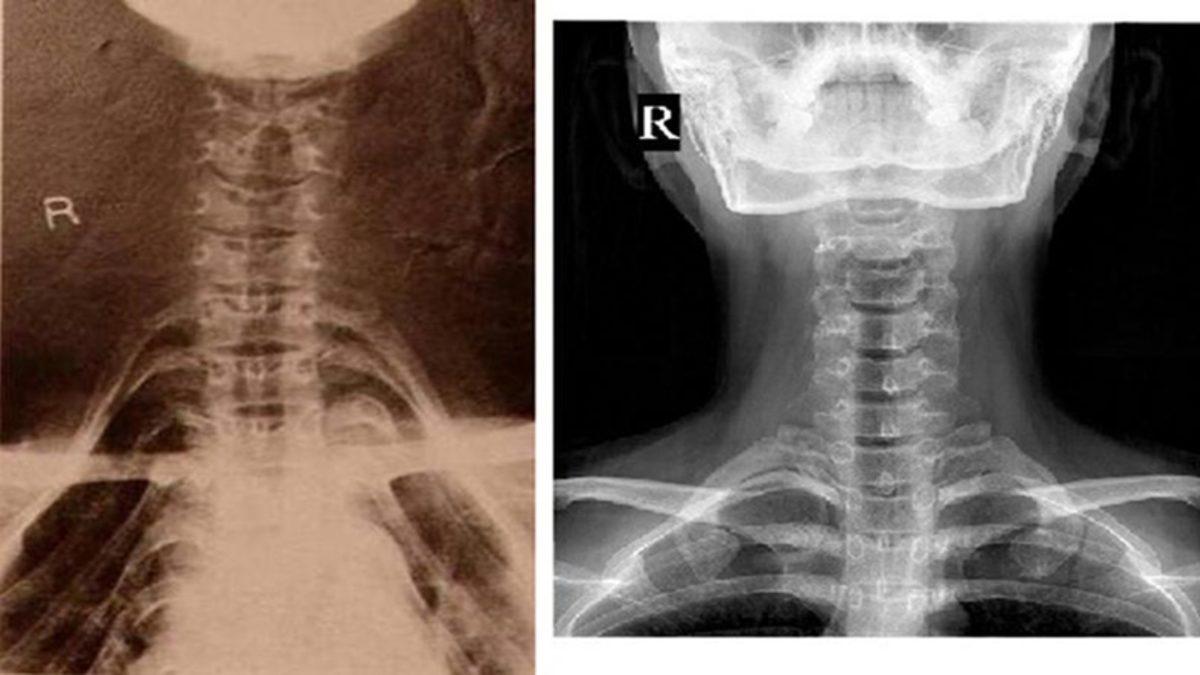

Devamlı olarak boyun bölgesinde halkaların kullanılması, omurgadaki omurların çökmesine neden oluyor. Bu nedenle, boyun uzatma uygulaması sağlık açısından hiç de olumlu sonuçlar doğurmuyor. Boyun bobinlerinin bazen 20 kilogram kadar ağırlığa sahip olduğu biliniyor. Boyun yapısının kırılganlığına karşı böylesi ağır bir aksesuarı takmak, güzellik uğruna yapılan acı girişimlerden biri haline geliyor.

Ayrıca bobinlerin ağırlığı köprücük kemiğini ittiği için göğüs kafesine baskı yapıyor. Bu bağlamda da köprücük kemiğinde deformasyonların oluşması kaçınılmaz oluyor. Hatta kadınlar, köprücük kemiklerinde oluşan yaraları önlemek için uyurken boyunlarını yapraklarla dolduruyor. Bu sayede köprücük kemiğine kademeli olarak yer değiştirme işlemi uygulanmış oluyor.